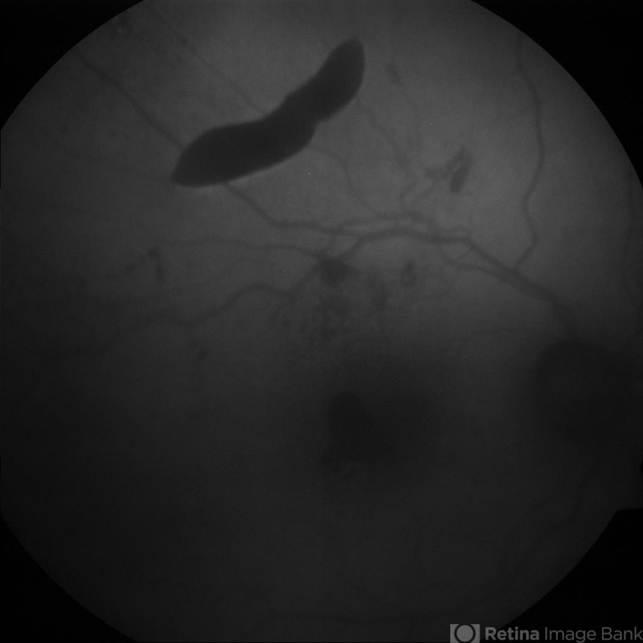

- Spontaneous RPE rip in NV AMD

- retinal pigment epithelium (RPE) tear, pigment epithelial detachment (PED)

- 80-year-old female with subfoveal occult CNV and large extrafoveal PED which underwent spontaneous RPE rip. Autofluorescence image shows hypoautofluorescence in crescentic area of absent RPE due to rip, and also RPE atrophy adjacent to fovea. Intervening small areas of hypoautofluorescence are due to subretinal haemorrhage.